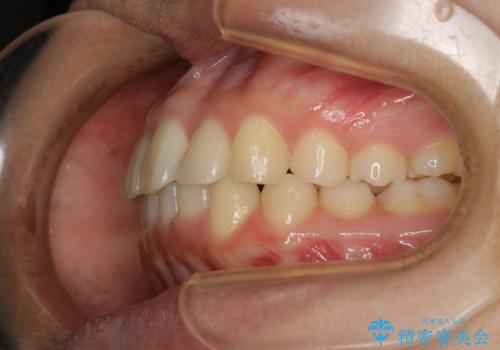

- 前歯が捻転していることを主訴に来院された方です。元々は部分矯正をご希望されていましたが、噛み合わせ等総合的に治療していくためインビザラインにて全顎的に治療を行うこととしました。

元々は上の前歯部の捻転のみの治療をご希望されていましたが、下の前歯もがたつきがあることや噛み合わせがかなり深いことを説明しました。後戻りのリスクを抑えるために全顎的な治療をご提案しました。

捻転していた上顎前歯部の仕上がりにこだわり、何度か修正を行ったため、満足のいく仕上がりになったと大変喜んでいただけました。